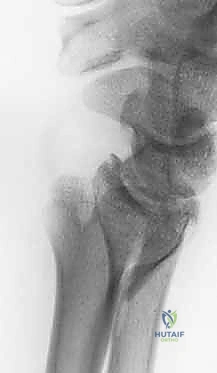

2. كسور رأس الزند (Ulnar Head Fractures)

رأس الزند هو الجزء المفصلي الدائري الذي يدور حوله الكعبرة.

* كسور مفصلية (Articular Fractures): تمتد خطوط الكسر لتشمل الغضروف المفصلي. إذا لم يتم إعادة العظام إلى وضعها التشريحي المثالي (Anatomic Reduction)، فإن المريض سيكون عرضة للإصابة بخشونة المفاصل المبكرة (Post-traumatic Osteoarthritis) وفقدان القدرة على تدوير الساعد.

3. كسور الجزء الكردوسي الكردوسي (Ulnar Metaphyseal Fractures)

الجزء الكردوسي هو العنق أو المنطقة الانتقالية التي تربط رأس الزند بجسم العظم (Diaphysis).

هذه المنطقة تحتوي على عظم إسفنجي (Cancellous bone) وهي عرضة للكسور المفتتة (Comminuted fractures) خاصة عند كبار السن المصابين بهشاشة العظام، أو في حالات الحوادث عالية الطاقة. الكسر هنا يؤدي إلى قصر في طول عظم الزند، مما يغير من ميكانيكية توزيع الأحمال في المعصم ويسبب متلازمة انحشار الزند (Ulnar Impaction Syndrome).

1. الأشعة السينية (X-rays): بوضعيات متعددة (أمامية خلفية، وجانبية دقيقة). الوضعية الجانبية الحقيقية (True Lateral) حاسمة لاكتشاف أي خلع جزئي في المفصل (DRUJ).

2. الأشعة المقطعية ثلاثية الأبعاد (3D CT Scan): تُستخدم في الكسور المفتتة أو كسور رأس الزند المفصلية المعقدة، حيث تعطي خريطة دقيقة للجراح قبل الدخول لغرفة العمليات.